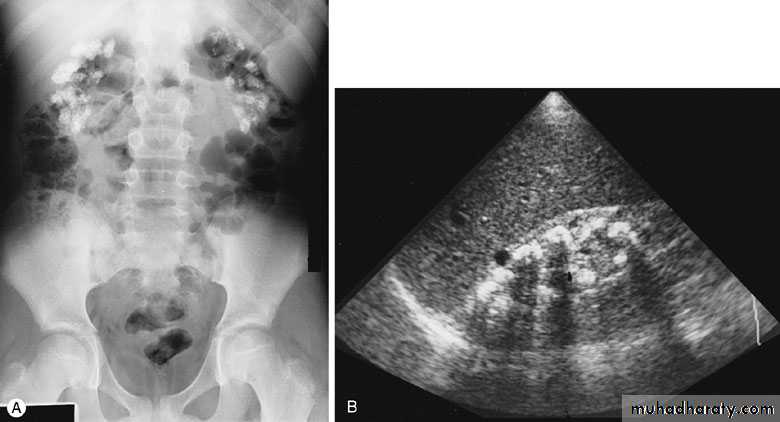

ULTRASONOGRAPHY (U/S )Structural study to differentiate cystic or solid masses, hydronephrosis, renal size, renal cortical thickness, and stones.

A calculus in the kidney casts an acoustic shadow

EXCRETORY UROGRAPHY (IVU , IVP, EXU )

These are organic chemicals to which iodine atoms are attached to absorb X-rays.Allows visualization of the entire urinary tract. The study provides demarcation of the renal parenchyma, the pelvicalyceal system, ureters, and bladder, providing both anatomic and functional information.

Number, size, site, function of the kidneys, anatomy of the collecting system, hydronephrosis, and filling defects, stones.

- After a plain film, iodine-containing contrast medium is injected intravenously and serial films are taken to follow its excretion by the kidneysThe nephrogram phase - on the initial film 1-3 minutes after injection, contrast medium is in the glomeruli and proximal tubules so that a clear image of the renal outline is obtained

The pyelogram phase - subsequent excretion of contrast medium outlines the collecting systems, renal pelvis, ureter and bladder, showing any structural abnormalities or filling defects